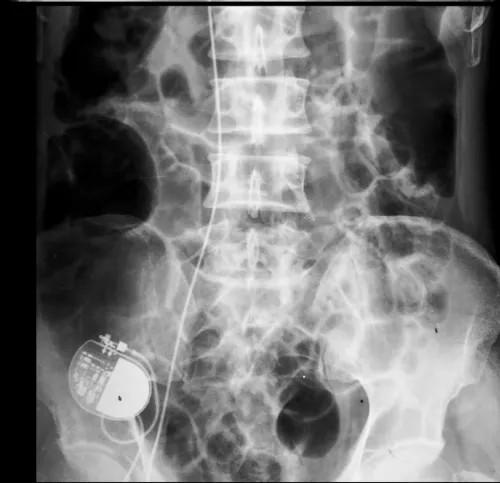

Due to exhaustion of other options, alternative access option was warranted. Therefore, pacemaker implantation via right external iliac vein (EIV) was considered. Under aseptic conditions and local anesthesia, a guidewire was placed in right common iliac vein by puncturing right femoral vein. With fluoroscopic guidance, right EIV was punctured 4 cm above midpoint of inguinal ligament after making an incision and dissecting upto fascial plane, with a 16-gauge needle taking care to avoid arterial puncture (Figure 2). Using a 16 cm peel away sheath, a long RV active fixation lead (Lead 5076, 85 cm, Medtronic) was screwed in RV apex after satisfactory pacemaker parameters were achieved. An alpha loop was made in right atrium to reduce risk of dislodgement (Figure 3). An inverted L-shaped dissection was done around puncture site and lead was doubly secured to external oblique fascia, at the puncture point, and, after making a U-turn superiorly using an additional suture sleeve (Figure 2, schematic). Lead was then tunneled subcutaneouly to the pacemaker pocket created by a separate incision over right lumbar region above external oblique fascia. A VVIR (RESR01-RELIA, Medtronic) pulse generator was also doubly secured to underlying fascia and subcutaneous tissue to prevent gravitational sagging. Finally, tissue and skin were sutured in layers and pressure dressing was done. Operating time was 78 minutes. Abdomino-thoracic radiograph showing final position of old leads and new implant is seen in figure 4.

Figure 4: Abdomino-thoracic radiograph showing final position of old leads and new implant.